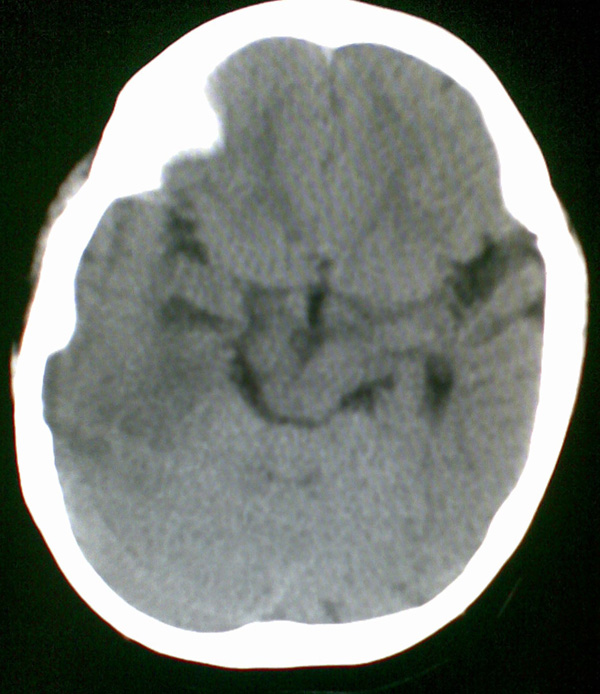

男4岁,反复抽搐多年,今早再次大抽搐,伴昏迷

1)右侧大脑半球大面积脑梗塞。2)双侧额叶脑软化灶。3)脑萎缩。

右侧半球梗塞,多发软化灶,考虑血管畸形继发,进一步检查。

右侧大脑半球大面积脑梗塞。双侧额叶脑软化灶。考虑血管畸形继发,建议进一步检查。